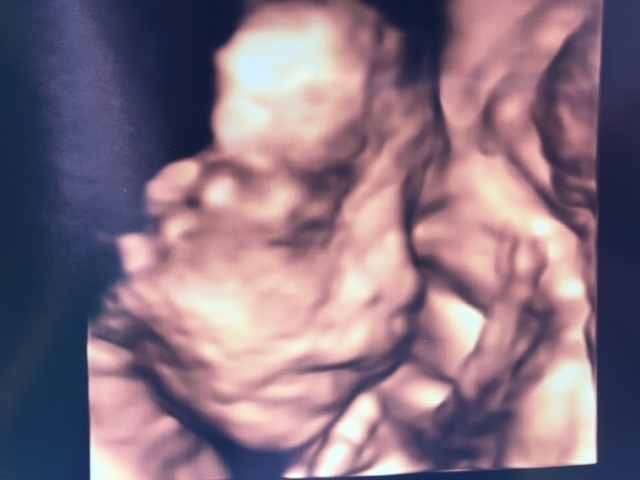

25週(25w・男の子)|takana さん(29歳)

エコー写真撮影時のエピソード:

検診の際いつも手で顔を隠していてはっきりと顔をみせてくれないのですが、初めてパパと4Dエコーを体験した時にタイミング良く赤ちゃんが微笑んでいる時の最高の一枚です。

エコーをしたくれていた院長先生も笑ってるねぇと言いながら写真とデーターを頂きました。